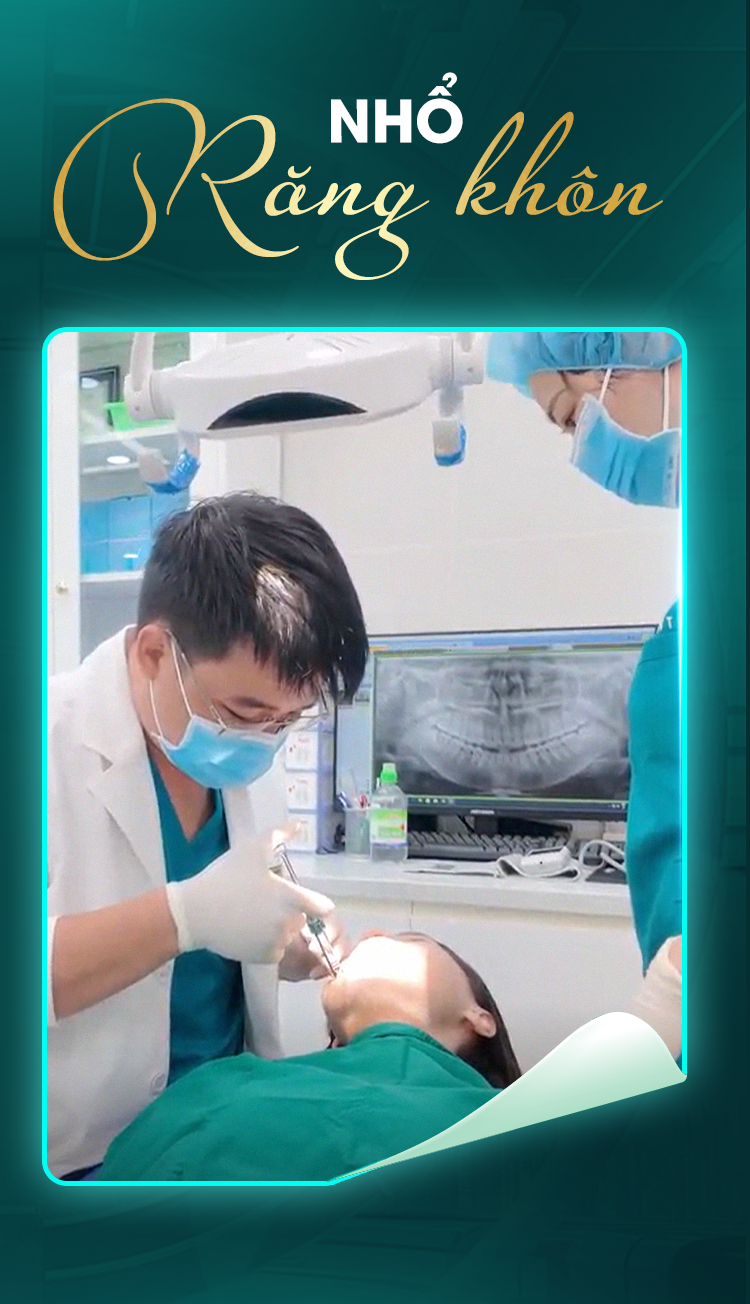

Nhổ răng khôn an toàn - Tạm biệt phiền toái

Tiểu phẫu răng khôn là quy trình loại bỏ những chiếc răng số 8 (răng khôn) mọc lệch, ngầm gây đau nhức, viêm nhiễm hoặc ảnh hưởng đến các răng kế cận, giúp bạn giải tỏa khó chịu và bảo vệ sức khỏe răng miệng.

Tiểu phẫu răng khôn